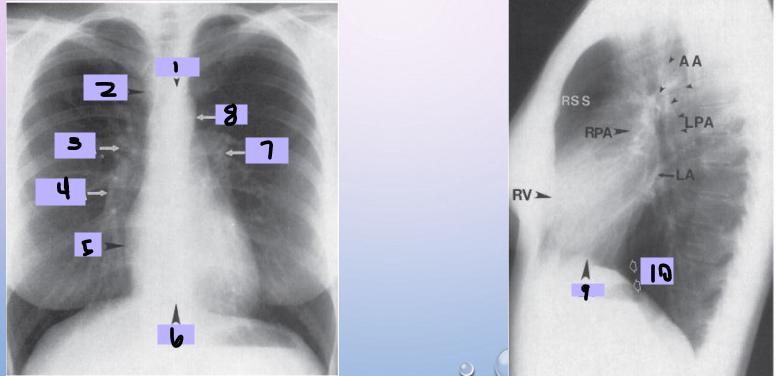

Aortic arch

#1

Superior vena cava

#2

Right pulmonary artery

#3

Right descending pulmonary artery

#4

Right atrium

#5

Right ventricle

#6

Left pulmonary artery

#7

Descending aorta

#8

Left ventricle

#9

Inferior vena cava

#10